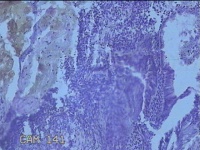

宫腔粘膜下肌瘤

性别

女

年龄

36岁

临床诊断

粘膜下肌瘤

一般病史

阴道流血42天。

标本名称

大体所见

灰白暗红色不规则组织1.3x0.5x0.2㎝一堆,切面均为灰白色结节状或编织状,质硬。